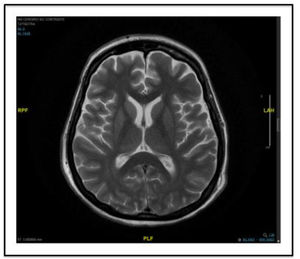

An MRI study yielded normal findings, and an EEG (Fig. 1) showed generalised delta activity with spike-wave patterns and dominant bifrontal projection. The patient was diagnosed with status epilepticus. Several AEDs and combinations of AEDs were administered: LEV at 4000 mg/day, lacosamide at 200 mg/12 h, brivaracetam at 100 mg/12 h, perampanel at 12 mg, valproic acid (VPA) at 4800 mg/day, and immunoglobulins (0.7 g/kg/day for 3 days) with propofol at 15 mL/h and midazolam (MDZ) at 12 mL/h. EEG activity did not improve. On day 14 of SRSE (26 weeks of gestation), due to the high doses of AEDs and anaesthetics, we opted to perform a caesarean section. A new EEG study performed after the procedure showed periodic, lateralised, predominantly bifrontal discharges (Fig. 1). In view of these findings, we added other AEDs: phenobarbital (4 mg/kg/day), a second cycle of immunoglobulins (0.7 g/kg/day for 3 days), and phenytoin (100 mg/8 h); the latter drug was quickly suspended because the patient presented signs of phenytoin hypersensitivity syndrome. Despite this treatment, EEG activity did not improve by day 25. Therefore, we induced barbiturate coma with infusion of thiopental (5 mg/kg/h) for 4 days, achieving no response. On day 30 of SRSE, AEDs were combined with ketogenic diet and methylprednisolone (1 mg/kg/day for 5 days). An MRI study performed 2 days later (Fig. 2), after withdrawal of propofol and MDZ, showed no new findings, and an EEG study showed that epileptiform activity had resolved.

(A) The first EEG study, showing generalised delta activity with spike-wave patterns and dominant bifrontal projection, consistent with status epilepticus. (B) EEG performed on day 15, after the caesarean section, showing periodic, lateralised, predominantly bifrontal discharges. (C) EEG performed on day 27, during barbiturate coma therapy, showing a burst-suppression pattern. (D) Final EEG, showing normal brain activity with occasional, predominantly temporal theta activity.

The patient's progression after resolution of SRSE was good: ketogenic diet was suspended and doses of VPA, phenobarbital, and methylprednisolone were gradually reduced, with no further seizures. At discharge, the patient presented completely normal cognitive function, with EEG showing normal activity with occasional, predominantly temporal theta activity (Fig. 1).